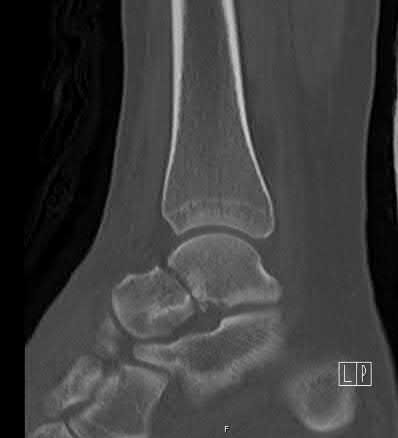

A 28-year-old male sustains a severe hyper-dorsiflexion injury to his ankle in a motor vehicle accident, resulting in a Hawkins Type III talar neck fracture. Which of the following arteries provides the predominant blood supply to the body of the talus, placing it at significant risk for avascular necrosis in this injury?

Explanation

The artery of the tarsal canal, which is a branch of the posterior tibial artery, provides the dominant blood supply to the talar body. In a Hawkins Type III fracture (talar neck fracture with subtalar and tibiotalar dislocation), the blood supply from the artery of the tarsal canal, the artery of the sinus tarsi, and capsular vessels are disrupted, leading to an avascular necrosis (AVN) rate approaching 100%.